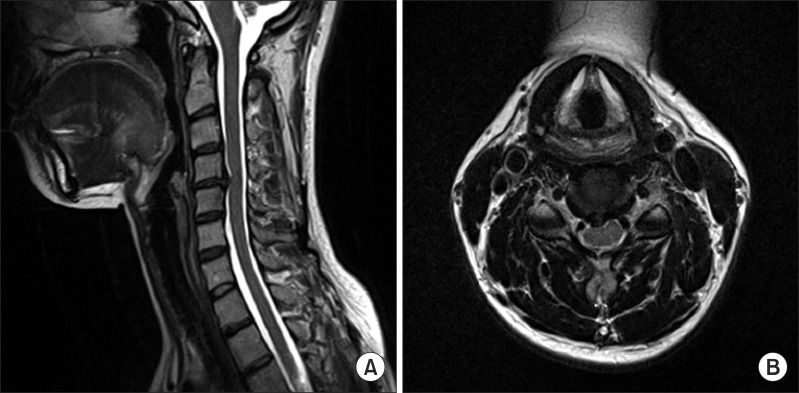

이러한 경우 정상적인 목척추 C 커브가 형성 되어있을 때보다 목이 앞으로 쭉 빠지는 거북목, 일자목이 되기쉽습니다.

거북목 일자목이 되면 정상 목 보다 머리무게의 6배 이상의 부하를 받게 됩니다. 그리고 거북목의 형태가 되면 목디스크도 쉽게 유발되고, 경추 후관절에도 문제를 일으켜 신경통의 양상도 띠게됩니다. 그러면 만성적으로 목어깨에 담이오는 증상이 생기게 됩니다.

경추 커브의 문제로 인한 만성적인 목어깨담은 주기적, 반복적으로 생깁니다.